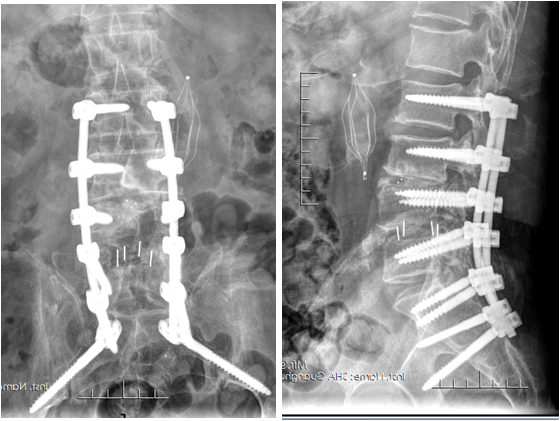

腰椎间盘突出症是一种常见的退行性腰椎病变,早期主要以保守治疗为主,包括改变不良姿势、加强腰背肌锻炼、止痛、营养神经、理疗等。若出现腰腿痛症加重,下肢肌力下降,二便功能障碍,保守治疗不能缓解,需考虑手术治疗。有很多人会问,手术治疗后是不是会一劳永逸,永不再发呢?答案是否定的。因为腰椎间盘突出症手术后还会面临两大问题: (1)腰椎间盘突出症术后复发,与年龄、肥胖、退变程度、骨质疏松症以及其它基础病等息息相关。 (2)腰椎间盘突出症术后邻椎病(也就是挨着原来突出节段椎间旁旁边的椎间盘再次突出而发病),近年越来越常见,主要原因是相邻腰椎不稳定或相邻椎间隙活动度异常增大等原因所导致,常需再次手术治疗。让我们看一个病人的治疗经过。 病人杨某某,男,70岁,因腰椎术后疼痛12年,加重2月入院治疗。病人2010年前因腰椎间突出症外院行腰45后路减压植骨融合内固定术,术后患者时有腰背部酸痛不适。2017年腰痛症状加重,伴下肢放射痛,再次行腰45翻修术+腰34后路减压植骨融合内固定,术后腰痛及下肢放射痛症状明显缓解。2022年6月腰痛加重,合并骨质疏松症,行密固达静滴治疗。同年8月腰痛再次加重,外院就诊提示内固定松动,再次行翻修及腰2到骶2节段内固定手术。术后腰骶部仍反复疼痛,下肢放射痛,行走不利。 杨先生入院后经温针灸、推拿手法行气活血,小针刀松解腰骶部瘢痕黏连,中药泡洗、热奄包外敷、中药内服等治疗加速淋巴回流,最终腰骶部疼痛基本消失,恢复了双侧下肢的行走功能,对治疗效果非常满意。 腰椎间盘突出症手术治疗不是一劳永逸,因此术后做好防护、避免相邻节段椎间盘再次突出引起临椎病显得非常重要。腰椎手术后需注意避免外伤、剧烈活动、久坐久蹲、弯腰劳累;要坚持锻炼腰背部肌肉;适当控制体重;出现腰腿部不适,要及时复查;调整心理,放松心情正常融入生活。 文中介绍的病人由于前三次手术创伤较大,手术部位存在严重疤痕组织,且内固定装置对腰骶部软组织刺激较大。瘢痕是人体修复创伤的产物,在正常的伤口愈合中,胶原的合成与降解维持平衡。病理性瘢痕组织发生过度增生,病人术后容易形成质地较为坚硬的增生性瘢痕,常感觉疼痛。术后增生性瘢痕形成后会影响淋巴回流,造成软组织肿胀。 这种多次手术后的情况,病人多不愿意再次接受手术治疗。此时应该针对软组织进行治疗。而小针刀治疗正是治疗软组织的有效方法。小针刀是在传统中医理论以及解剖学、生理病理学、现代生物力学等现代医学理论指导下, 融合了中医的针灸针和西医的手术刀的长处而形成的中医微创技术,以组织剥离的手法, 达到松解黏连的目的。针刀直径一般只有0.5~0.8mm, 损伤非常小;加之针刀的针柄和针刃是在同一个平面内, 可以通过针柄控制针刃在人体内的方向, 治疗非常安全,越来越受到病人的欢迎。而术后瘢痕黏连,是针刀临床的最佳适应证之一,进针点一般在瘢痕局部及周围。针刀的治疗原理主要是通过闭合性松解微创操作,切开瘢痕、分离粘连与挛缩、疏通堵塞,从而改变软组织的病理状态,恢复软组织和骨关节的力学平衡,以消除症状。 腰椎间盘突出症手术治疗并不是一劳永逸的。手术之后,在做好防护的同时,配合小针刀等其它有效治疗手段也显得非常重要。 附图: 2010年L4/5术后,2017年正侧位摄片 2017年6月L3/4、L4/5术后正侧位摄片 2022年8月腰痛L2-S2术后,可见骶椎软组织覆盖薄弱 作者:上海中医药大学附属光华医院 康复科 王世辉 程少丹 延伸阅读